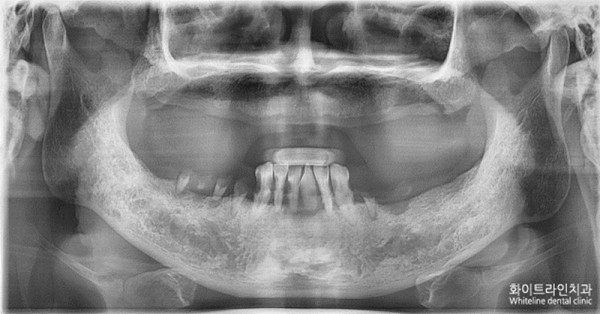

1. 첫 내원 및 치료계획 상담 - 2016년 11월 2일

상악은 무치악(치아가 전혀 없는)상태로 틀니를 사용하고 계셨고

하악은 충치와 치주염(하악 전치부는 모두 동요도가 심한 상태)으로 많이 좋지 않은 상태였습니다

상악 8개, 하악8개 동시 식립 위치를

파노라마 사진 상에 잡아놓은 사진입니다

노란 임플란트 모형 중간중간에 세로의 빨간 선에서 끊어 보철을 연결하기로 했습니다

하악에는 뼈의 결손부들이 몇군데 보여 뼈이식을 동반하기로 했습니다.